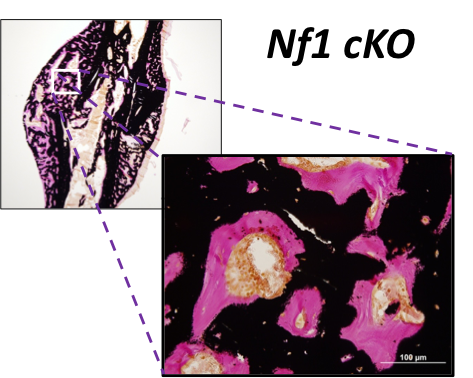

By studying how Nf1 loss-of-function impacts the maturation and function of chondrocytes and osteoblasts, we seek to understand the etiology of the most problematic skeletal maladies associated with neurofibromatosis type 1 (NF1), which includes dystrophic scoliosis, tibia bowing and recalcitrant bone healing.